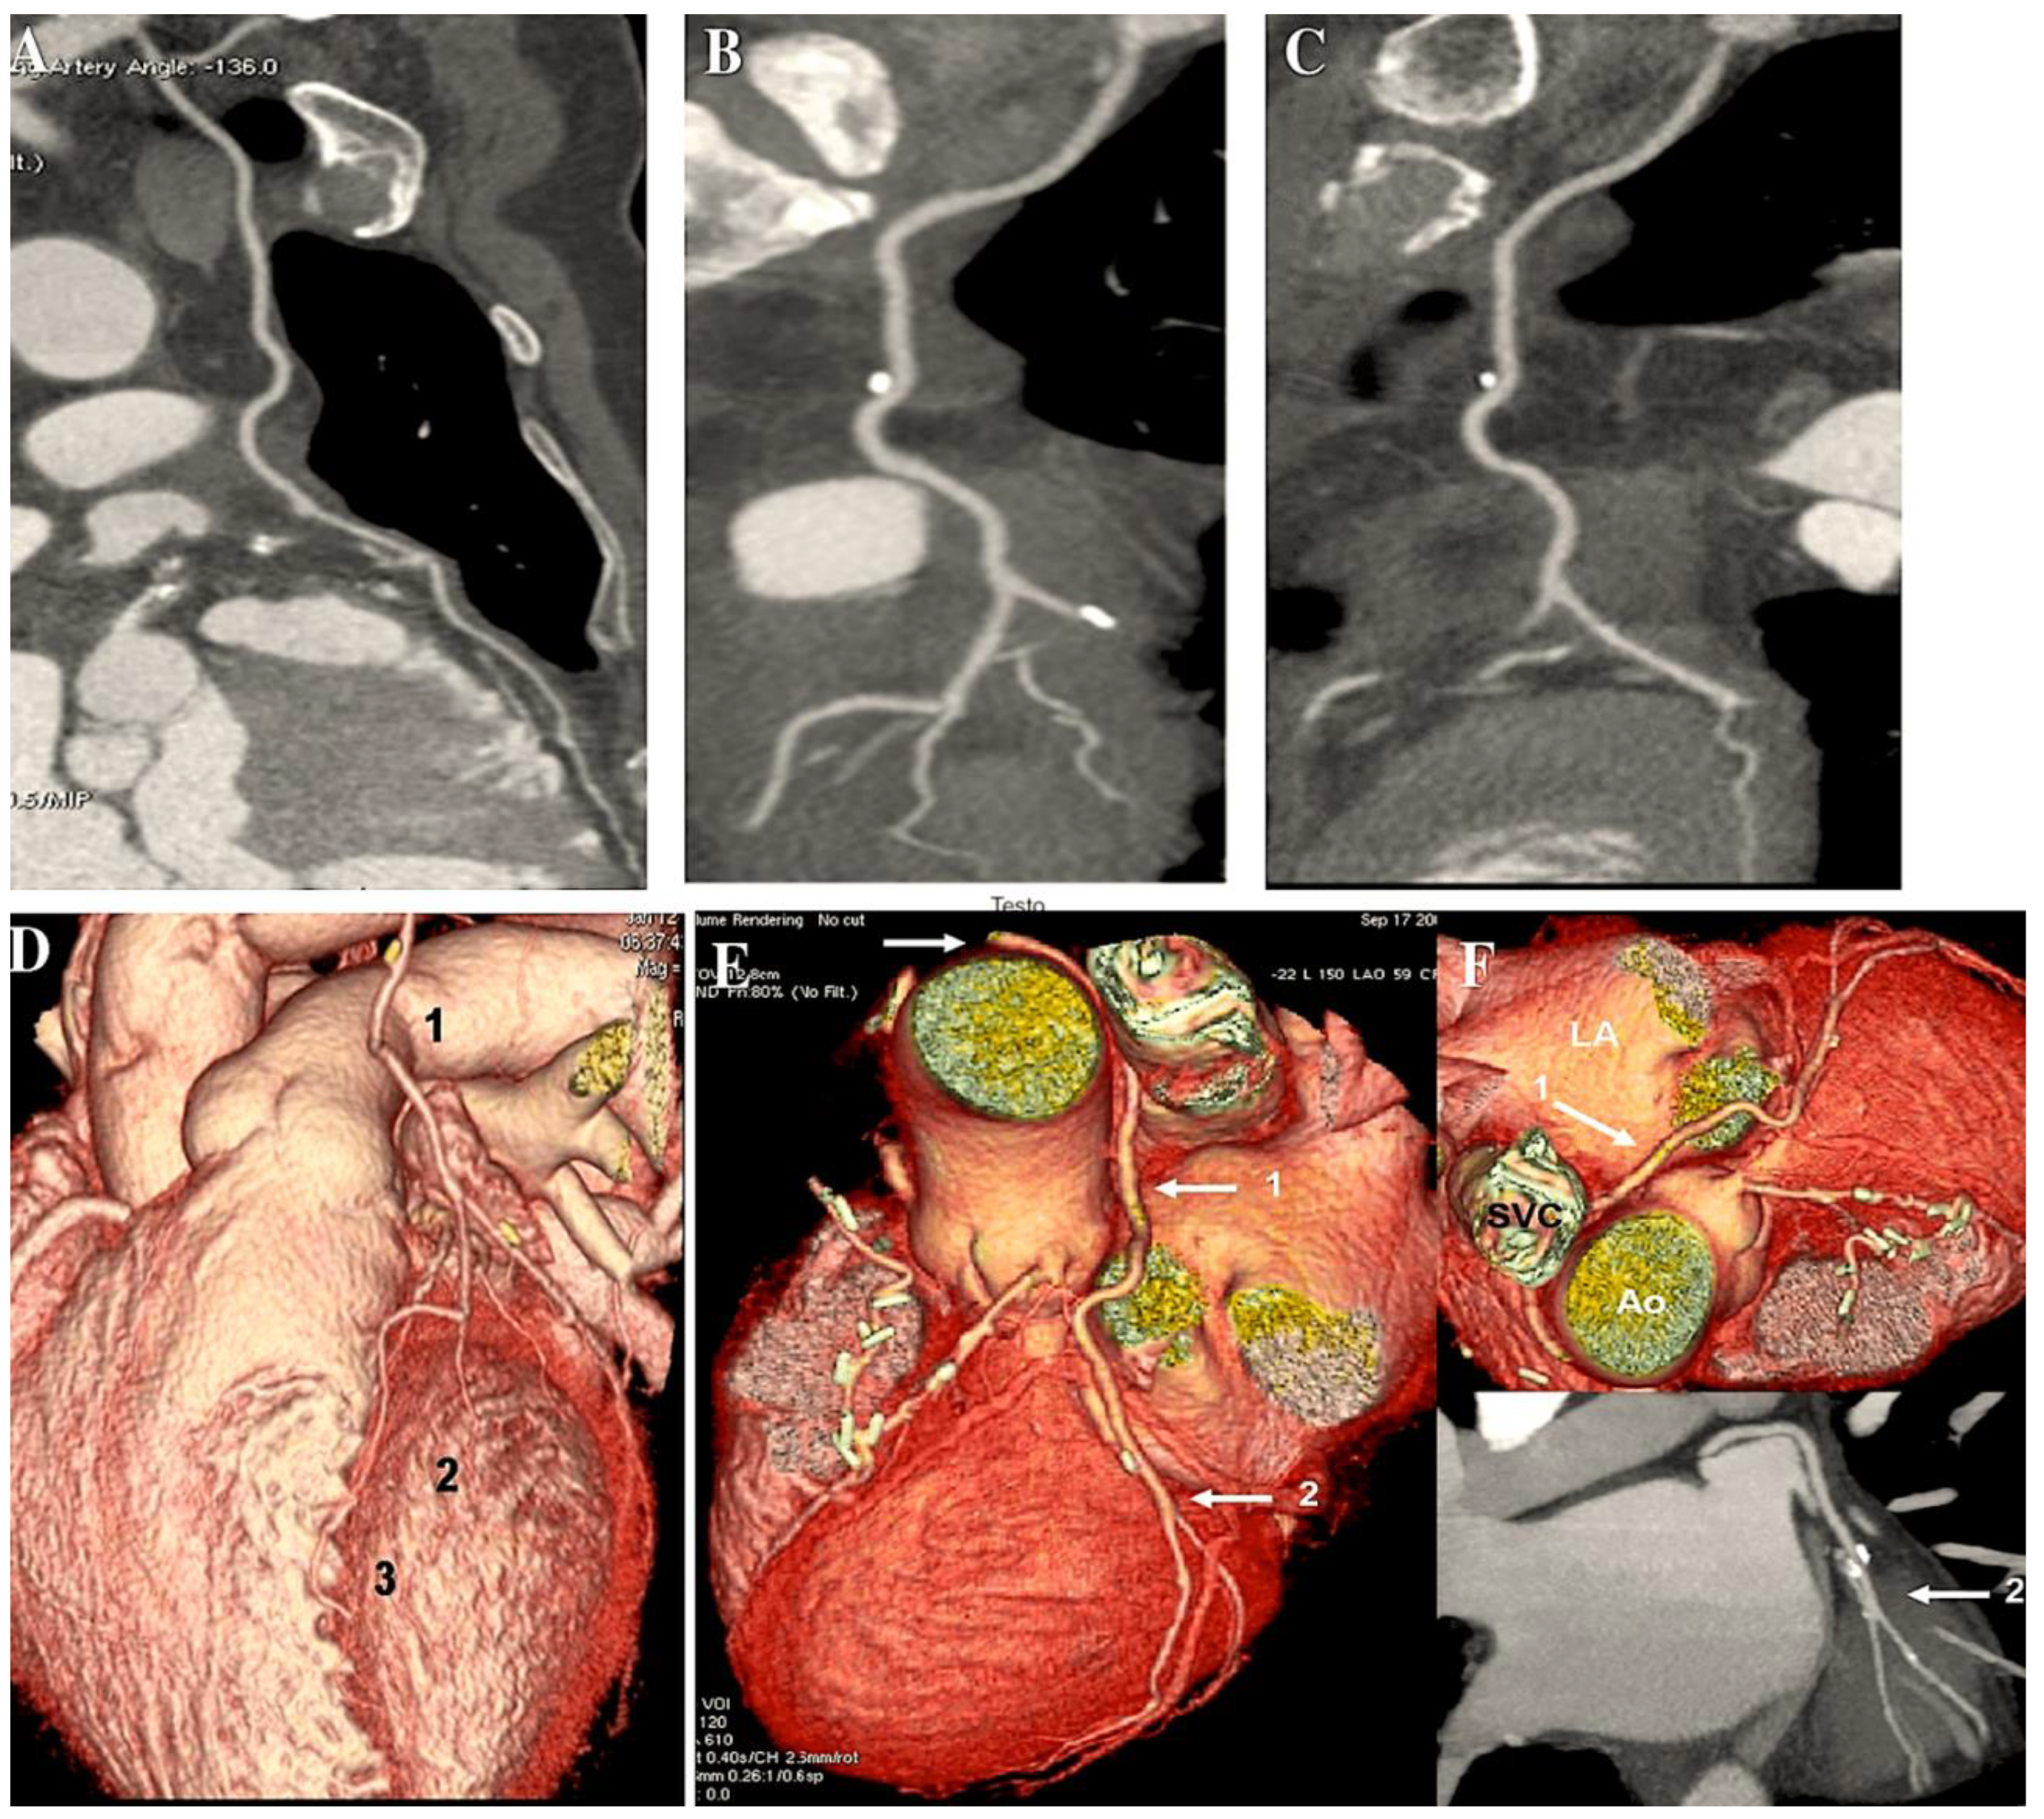

- Di Lazzaro D, Ragni T, Di Manici G, Bardelli G, Da Col U, Grasselli F, Antoniella A, Papa W, Crusco F, Giovagnoni A. Noninvasive midterm follow-up of radial artery bypass grafts with 16-slice computed tomography. Ann Thorac Surg 2006. 82:44-50. [CrossRef]

- Ropers D, Pohle FK, Kuettner A, Pflederer T, Anders K, Daniel WG, Bautz W, Baum U, Achenbach S. Diagnostic accuracy of noninvasive coronary angiography in patients after bypass surgery using 64-slice spiral computed tomography with 330-ms gantry rotation. Circulation. 2006;114:2334-41 . [CrossRef]

- Feuchtner GM, Schachner T, Bonatti J, Friedrich GJ, Soegner P, Klauser A, zur Nedden D. Diagnostic performance of 64-slice computed tomography in evaluation of coronary artery bypass grafts. Am J Roentgenol. 2007; 189:574-80. [CrossRef]